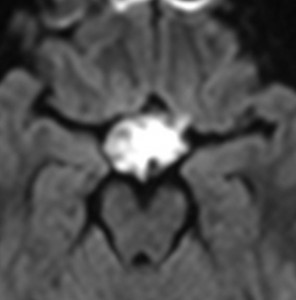

小脳類皮のう胞

偶然発見された女の子のものです。左のCTで石灰化があります。右の拡散強調画像 DWI で白く高信号に描出されるのが特徴です。手術では腫瘍内部に毛髪がたくさんありました。後下小脳動脈に強く癒着していて,脳軟膜からの剥離もできませんでしたが,完全摘出しました。無症状でも”完全”摘出 complete removal するべきです。